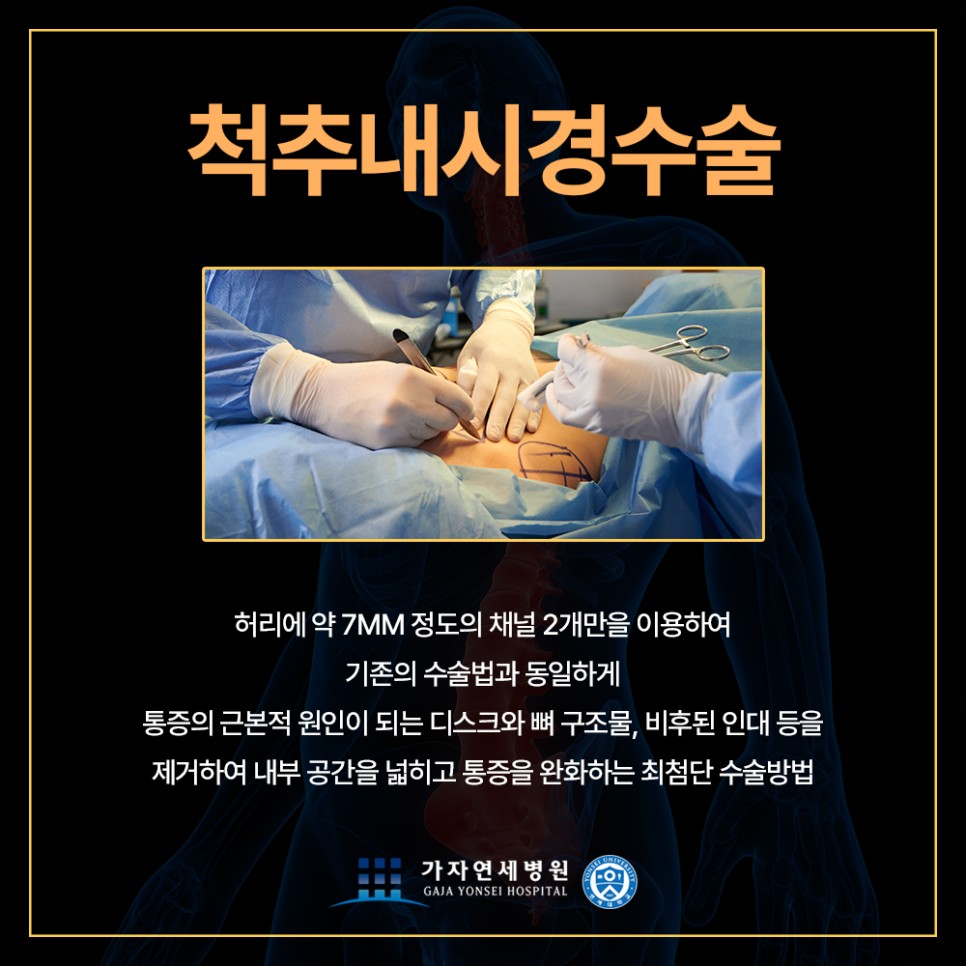

비수술적 치료의 범위를 벗어난 허리디스크 증상을 보이시는 분들이나 만성질환, 고령 등의 이유로 전신마취가 어려운 환자, 심각한 척추관협착증 환자와 같이 중증도 이상의 환자의 경우 수술치료가 필요할 수 있는데요, 허리디스크 김포가자연세병원에서는 수술적치료로써 미세현미경 수술과 척추내시경 수술을 진행하고 있습니다.

척추내시경이란 척추 마취 후 허리에 약 7mm 정도의 채널 2개를 이용해 근본적인 디스크, 비후 된 인대, 뼈 등을 제거하는 수술치료방법으로 2~3일의 입원 기간이 소요되지만 수술 당일부터 보조기를 착용하여 당일 보행에도 무리가 없어요.

허리디스크 김포가자연세병원은 무균수술 시스템으로 수술실에서 환자의 척추 상태와 연령, 생활패턴까지 고려하여 1:1 개인 맞춤 척추내시경 수술을 진행하고 있어요. 1cm 이내의 작은 상처로 흉터가 거의 남지 않고, 기존의 척추수술과 동일하게 통증의 근원적인 제거가 가능한 장점이 있죠. 퇴원 후에도 외래진료를 통해 회복 단계에 맞는 맞춤 관리도 시행한답니다.